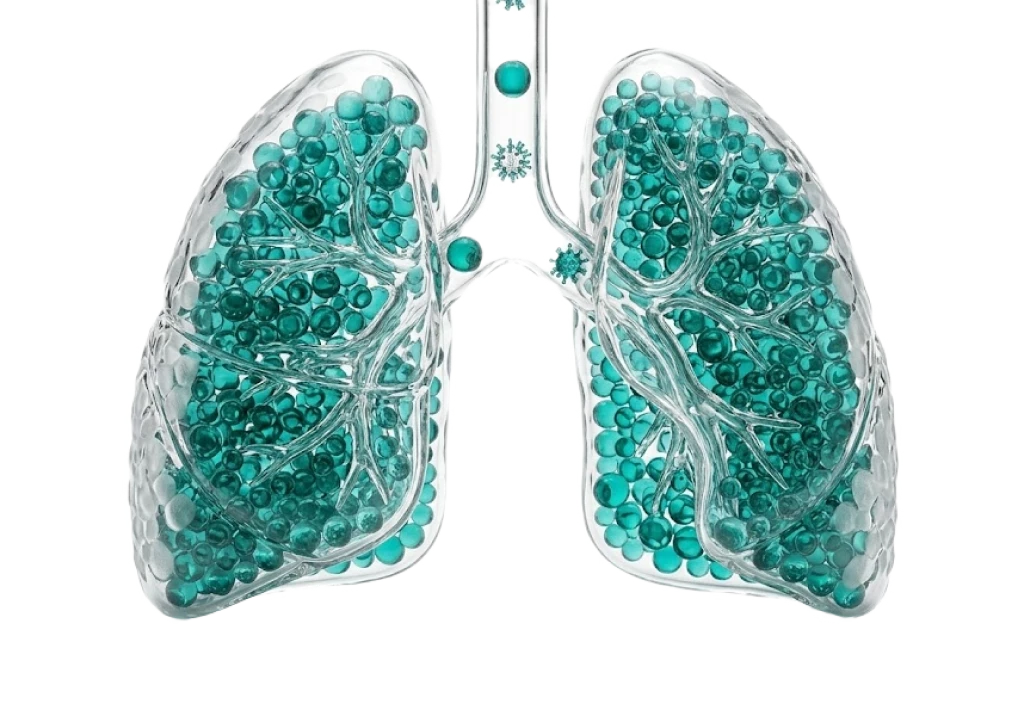

Пульмонология